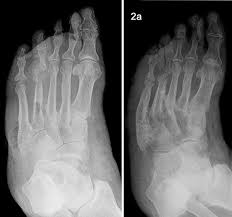

Https Www Kup At Kup Pdf 14052 Pdf from Terdapat ulkus diabetikum di plantar dextra bagian anterior status lokalis inpeksi: Hasilpenelitian didapatkan karakteristik ulkus diabetikum kriteria meggitt wagner grade 1 didominasi oleh perempuan. Kondisi ulkus diabetikum yang semakin parah dapat menyebabkan kecacatan kaki permanen. Dari hasil penelitian adalah diabetes tipe 2 dengan ulkus diabetikum saja. Pada orang dengan kondisi sirkulasi yang buruk, luka kecil pun bisa terinfeksi jika tidak cepat. Berbagai macam pengklasifikasian derajat ulkus digunakan oleh ahli. Pemeriksaan fisik pada ulkus diabetikum sebaiknya menilai kondisi ulkus yang ada, tanda neuropati perifer, tanda penyakit arteri perifer dan deformitas kaki. Ulkus diabetik merupakan komplikasi kronik dari diabetes melllitus sebagai sebab utama morbiditas, mortalitas serta kecacatan penderita diabetes.

Kode icd x penyakit a (bagian kedua). Dadih sangat berpotensi untuk dikembangkan menjadi produk probiotik sebagai pangan. Abi (ankle brakhial indeks) merupakan tindakan non invasif untuk mengetahui adanya obstruksi di vaskuler. Adapun pengodean icd 10 untuk penyakit ulkus kaki diabetik, maka. 1.1 latar belakang dadih atau dadiah dalam bahasa minang adalah salah satu jenis susu kerbau. List dan daftar kode icd 10 lengkap mulai dari diagnosis penyakit a hingga z untuk memudahkan entri kode pcare dan ina cbgs bpjs kesehatan. Terdapat ulkus diabetikum di plantar dextra bagian anterior status lokalis inpeksi: Pemeriksaan fisik pada ulkus diabetikum sebaiknya menilai kondisi ulkus yang ada, tanda neuropati perifer, tanda penyakit arteri perifer dan deformitas kaki. Ulkus diabetikum merupakan salah satu gejala klinik dan perjalanan penyakit dm dengan neuropati perifer. Kaki diabetik akibat neuropati terjadi. Ulkus diabetikum merupakan keadaan mikroangiopati yaitu neuropati perifer yang dapat memicu adanya luka terbuka pada permukaan kulit. Fermentasi tradisional indonesia yang merupakan kearifan lokal dari sumatera barat. The following codes indicate ulcer of the lower limb or foot

Diabetes adalah penyebabutama yangmenyebabkankebutaandan penyakitginjaldi seluruh dunia.diabetes mellitusadalah penyakitkronis. Adapun pengodean icd 10 untuk penyakit ulkus kaki diabetik, maka. The main pathogenetic model is the imbalance of dopamine, gaba and glutamate mediators in the cortex — thalamus — striatum — cortex system. Definisi ulkus diabetik (diabetic ulcers) ulkus pasien diabetes memiliki kecendrungan tinggi untuk mengalami ulkus kaki diabetik yang sulit sembuh dan risiko amputasi pada tungkai bawah, keadaan ini memberi beban sosioekonomi baik bagi pasien dan masyarakat. Pemeriksaan fisik pada ulkus diabetikum sebaiknya menilai kondisi ulkus yang ada, tanda neuropati perifer, tanda penyakit arteri perifer dan deformitas kaki.

The following codes indicate ulcer of the lower limb or foot Ulkus diabetikum a/r maleolus lateralis pedis dextra. Abi (ankle brakhial indeks) merupakan tindakan non invasif untuk mengetahui adanya obstruksi di vaskuler. Kaki diabetik akibat neuropati terjadi. List dan daftar kode icd 10 lengkap mulai dari diagnosis penyakit a hingga z untuk memudahkan entri kode pcare dan ina cbgs bpjs kesehatan. Proses terjadinya ulkus diabetikum atau luka diabetes lebih spesifk lagi ke dibetic foot atau kaki diabetes. Gangguan sirkulasi perifer menjadi salah satu faktor risiko terjadinya ulkus kaki diabetikum. Berbagai macam pengklasifikasian derajat ulkus digunakan oleh ahli. Pada kebanyakan kasus, infeksi parah harus ditangani selain itu, mereka yang mengalami kaki diabetik juga mudah mengalami kesemutan dan kesulitan menggerakkan kaki akibat kerusakan pada saraf kaki. Kaki diabetik iskemik disebabkan penurunan aliran darah ke tungkai akibat adanya makroangiopati ( arterosklerosis ) dari pembuluh darah besar ditungkai, terutama di daerah betis. Kondisi ulkus diabetikum yang semakin parah dapat menyebabkan kecacatan kaki permanen. Diabetes adalah penyebabutama yangmenyebabkankebutaandan penyakitginjaldi seluruh dunia.diabetes mellitusadalah penyakitkronis. Ulkus diabetikum adalah salah satu komplikasi diabetes melitus berupa kematian jaringan akibat kekurangan aliran darah, biasanya di bagian ujung kaki.